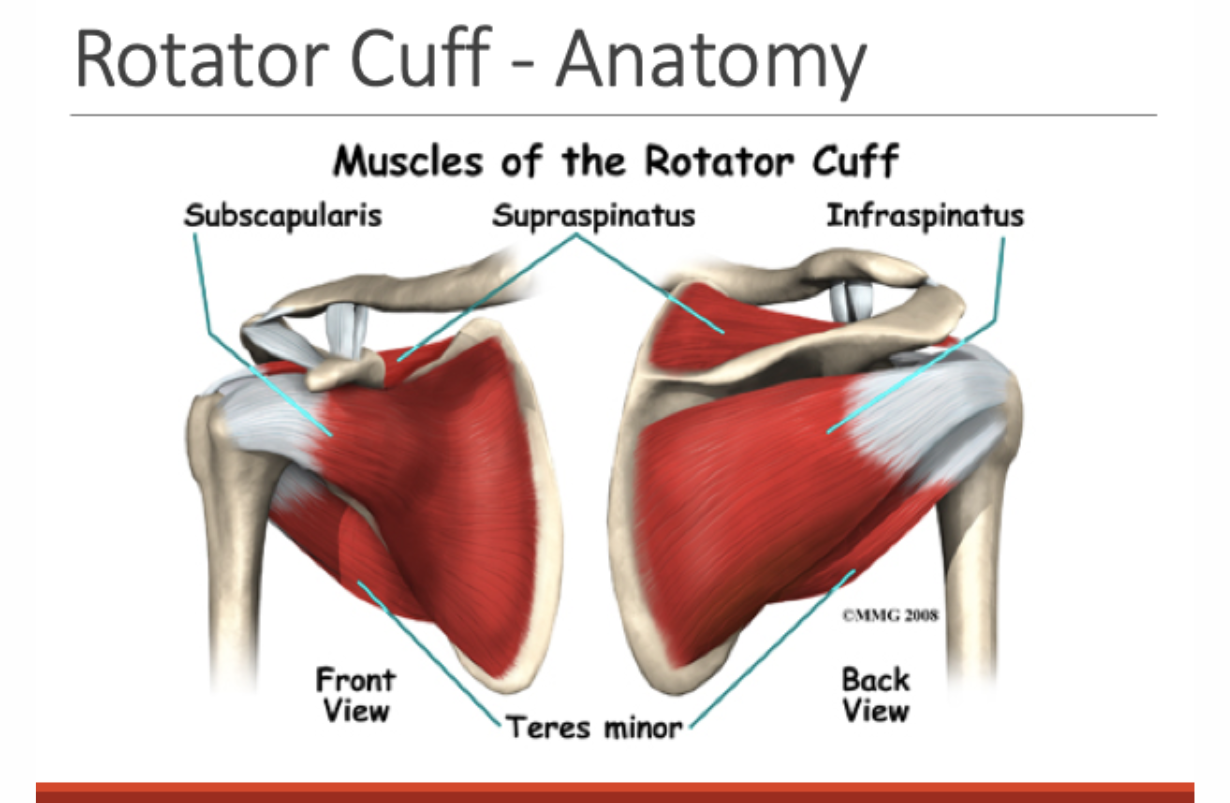

Rotator Cuff Syndrome

DEFINITION: Tear or total break in one or more shoulder muscles, the supraspinatus, infraspinatus, subscapularis or teres minor. More than 90% of the time it is the supraspinatus. BENEFICIAL POSES: Iyengar Headstand (with shoulders elevated) and variations lifting shoulders while inverted with thighs supported on a chair, or triangular forearm support done in tilted standing position with forearms against the wall toward which one is tilted. TECHNIQUE: After staying in one of the positions with shoulders drawn away from the ears and supraspinatus unengaged for 45 seconds, one must quickly stand up and then bravely and fearlessly abduct the arms rapidly to overhead at least twice, and flex the shoulders, bringing the arms in front and overhead at least twice in rapid succession. This requires courage because these are exactly the movements that were painful just a minute before. See video below. EXPLANATION: Holding the shoulders aloft while inverted activates the subscapularis, which can work to elevate the arm (when standing up) by pulling the head of the humerus down while the deltoid holds the first part of the bone steady. This raises the shaft the way a cantilever bridge, or "teeter-tauter" works. The deltoid acts as a fulcrum, holding the first part of the humerus steady while the subscapularis pulls the head of the bone down. This raises the shaft of the humerus up. Once learned, possibly by a mechanism similar to operant conditioning, the person keeps using this painless, effective way of lifting the arm, which supplants the painful, ineffective use of the torn supraspinatus. People have been followed for more than 15 years and remain with full active painless range of motion although the supraspinatus muscle may not heal. REFERENCE: Fishman LM.. “Headstand in the treatment of rotator cuff syndrome – Sirsasana or surgery. Journal of the International Association of Yoga Therapists. (16): October 2006. 137-45.